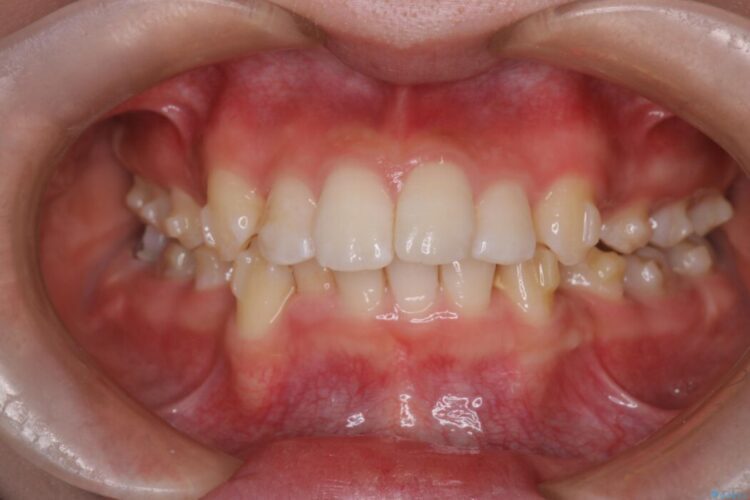

治療後について

長年の悩みだった重度の乱れが解消され、口元の突出感もすっきり改善。見た目も機能も安定した、理想的な歯並びを獲得していただけました。